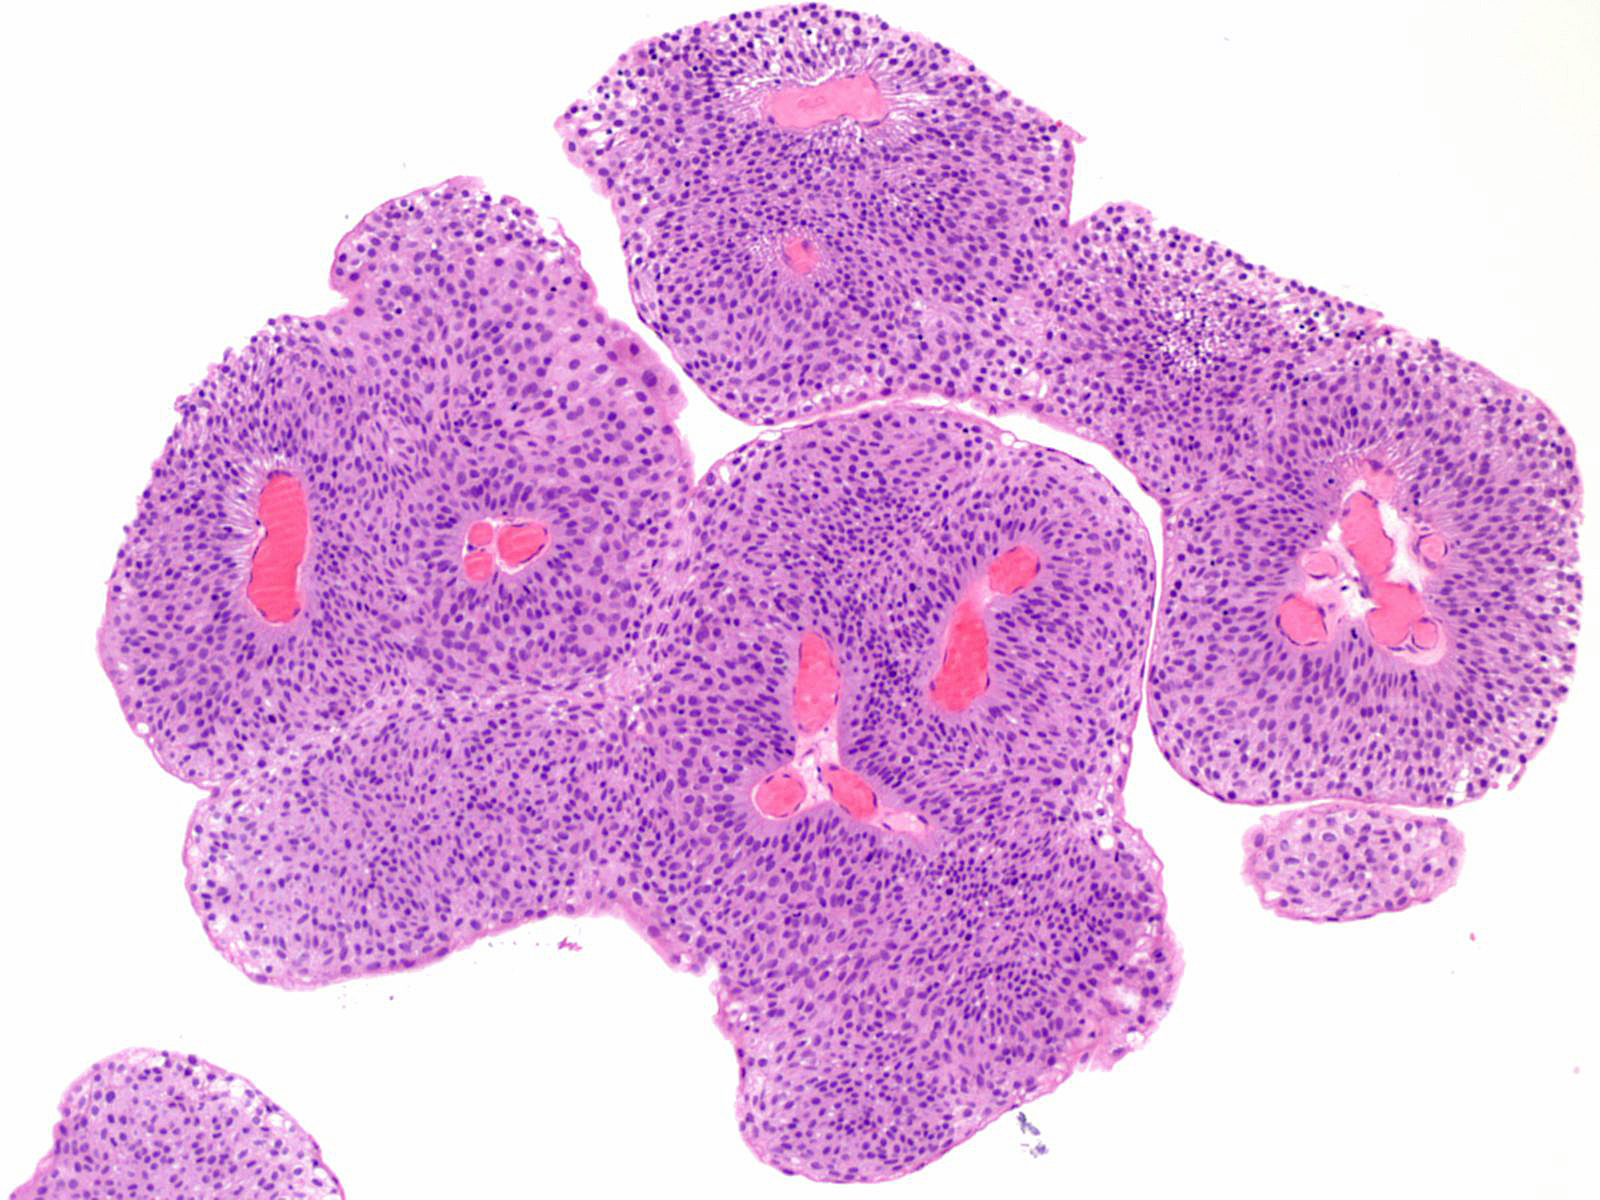

Bladder Papillary Lesions

Case ID: 121